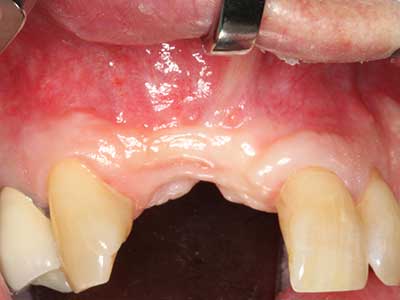

When surgical procedures are performed on bone in the immediate vicinity of sensitive structures such as blood vessels or nerves, rotary instruments pose a significant risk of iatrogenic injury. Piezoelectric devices can be helpful for preparation of bone covers and removal of hard tissue close to nerves, particularly for exposure of nerves after iatrogenic injury but also during nerve lateralization for resective and reconstructive procedures or implant placement (Fig. 17-20). Light contact between the piezotip and the nerve does not generally result in damage but proceeding incautiously with saw-like motions or attachments where a residual bone substrate remains may cause temporary or even permanent nerve damage. However, the risk of damage is considered to be substantially lower than when using saws or milling instruments (Pereira, Gealh et al. 2014).